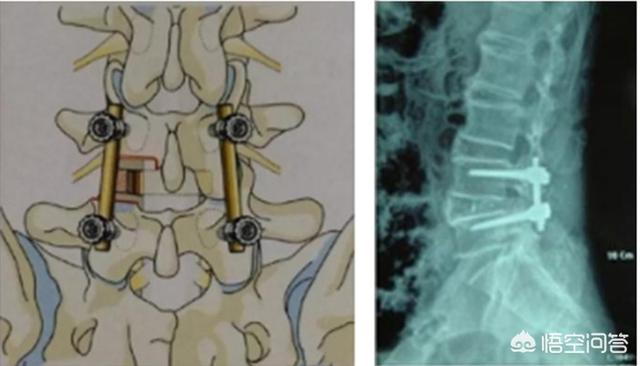

2. décompression postérieure par plaque ouverte, fixation interne par vis pédiculaire.

En général, les procédures qui ne peuvent pas être résolues par une laminectomie peuvent être résolues par cette procédure.

Pourquoi existe-t-il deux approches chirurgicales ?

En effet, lorsqu'une hernie discale est retirée, une partie de la stabilité entre les vertèbres est perdue, ce qui peut entraîner des douleurs lombaires et une dégénérescence accélérée du dos. Ainsi, pour les patients plus âgés, qui ont déjà un dos instable, il est possible de subir une chirurgie de fusion unique, qui consiste à retirer tous les disques, à placer un dispositif de fusion et à fixer le dos à l'aide d'une fixation interne. Les risques de cette procédure sont plus importants que l'ablation seule ; en effet, la procédure comporte plus d'étapes et prend plus de temps.